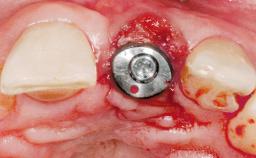

A 42-year-old female patient was referred to our clinic at the School of Dentistry of the University of São Paulo in November 2004, presenting a deficient restoration in the upper left central incisor. The clinical examination revealed no gingival retraction or any signs of gingival inflammation and, therefore, previous periodontal treatment was not considered. The patient presented a high lip line at full smile and a thin tissue biotype. This combination characterized a high-risk situation from an anatomic point of view, which required careful preoperative planning and cautious surgical execution.

Placement Protocol Immediate implant placement

Tooth Site Maxillary incisor or canine

Socket Morphology Single-root socket

Socket Integrity Sufficient, with intact bone walls